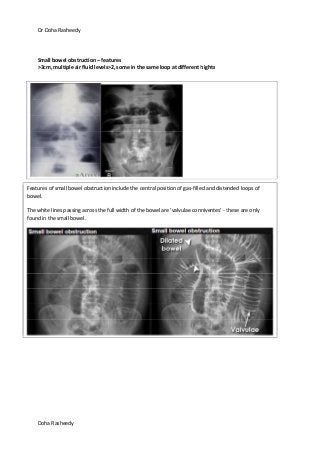

Small bowel obstruction – features

>3cm, multiple air fluid levels>2, some in the same loop at different hights

Features of small bowel obstruction include the central position of gas-filled and distended loops of

bowel.

The white lines passing across the full width of the bowel are 'valvulae conniventes' - these are only

found in the small bowel.

Small bowel obstruction

Small bowel obstruction can be visualised

on an AXR as dilatation of the small

bowel (>3cm). The valvulae conniventes

are much more visible and have what is

referred to as a “coiled spring

appearance”.